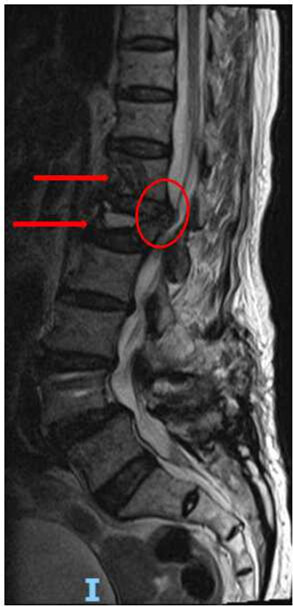

陈奶奶骨折后MRI结果,示骨折部位以及脊髓压迫

看这个MRI和CT的结果,T12和L1这两个地方的压缩性骨折肯定没跑了,但是这个骨折有一小部分压迫到了脊髓和神经,失去了打骨水泥这种微创手术的机会。不得不做了一个大的开放性的后路T12、L1椎体骨折切开复位内固定术。又给加了5对也就是10个钉子在里面。